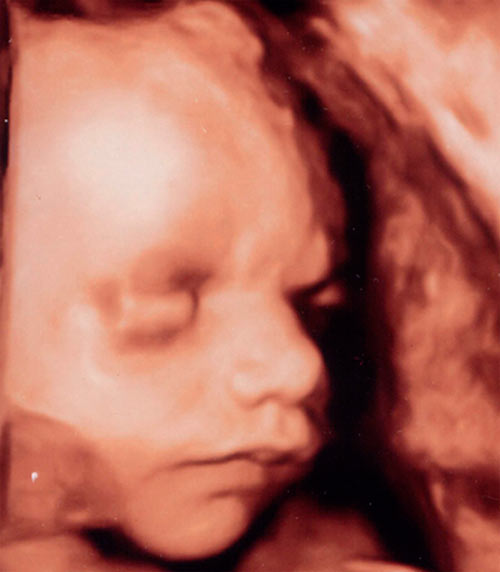

Photo échographique la 29e semaine:

Alors bébé bouge comme ça 🙂